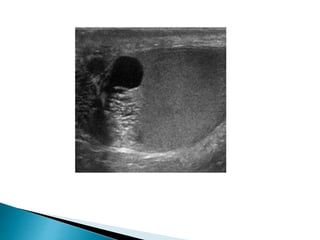

 Sonographically it is seen as an anechoic area

partly surrounding the testicle

 Formation offluid between the two layers (visceral and parietal) of the tunica vaginalis.  Mostly idiopathic  May develop as a result of infection (epididymo-orchitis), trauma, malignant testicular tumour or infarction (including torsion).  Sonographically it is seen as an anechoic area partly surrounding the testicle